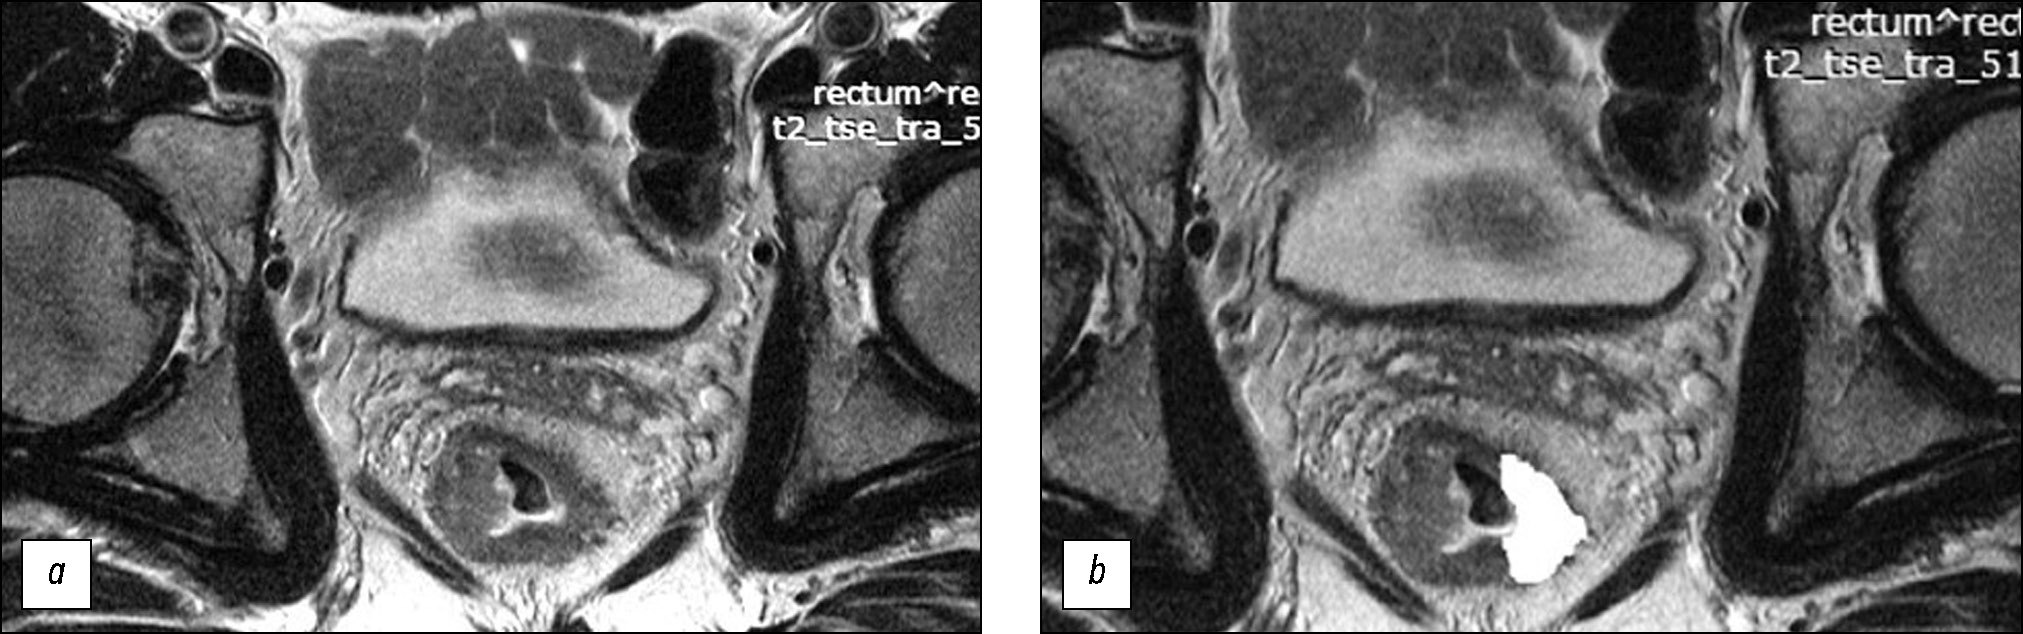

Цель исследования ― оценить текстурные характеристики местно распространённого рака прямой кишки на первичном Т2-взвешенном изображении (Т2-ВИ) в качестве потенциального фактора прогноза эффективности стандартной неоадъювантной химиолучевой терапии и разработать на их основе систему прогнозирования эффективности такого лечения.

Материалы и методы. Включённые в ретроспективное исследование пациенты с местно распространённым раком прямой кишки, получившие комбинированное лечение с неоадъювантной химиолучевой терапией (n=82), были разделены на обучающую (n=58) и контрольную (n=24) выборку. Для текстурного анализа использовали первичное Т2-ВИ высокого разрешения на уровне центра опухоли, ориентированное перпендикулярно стенке кишки. Текстурный анализ выполняли статистическим методом второго порядка на основе матрицы совместной встречаемости уровней серого (GLCM) с помощью компьютерной программы MAZDAver. 4.6 с расчётом 11 параметров текстуры. После морфологической оценки операционных препаратов в обучающей выборке выявлены достоверно различающиеся параметры текстурного анализа для групп пациентов, ответивших (группа хорошего прогноза) и не ответивших (группа плохого прогноза) на лечение, на основе чего создана балльная система оценки эффективности неоадъювантной химиолучевой терапии. Система протестирована на контрольной выборке с определением параметров диагностической эффективности.